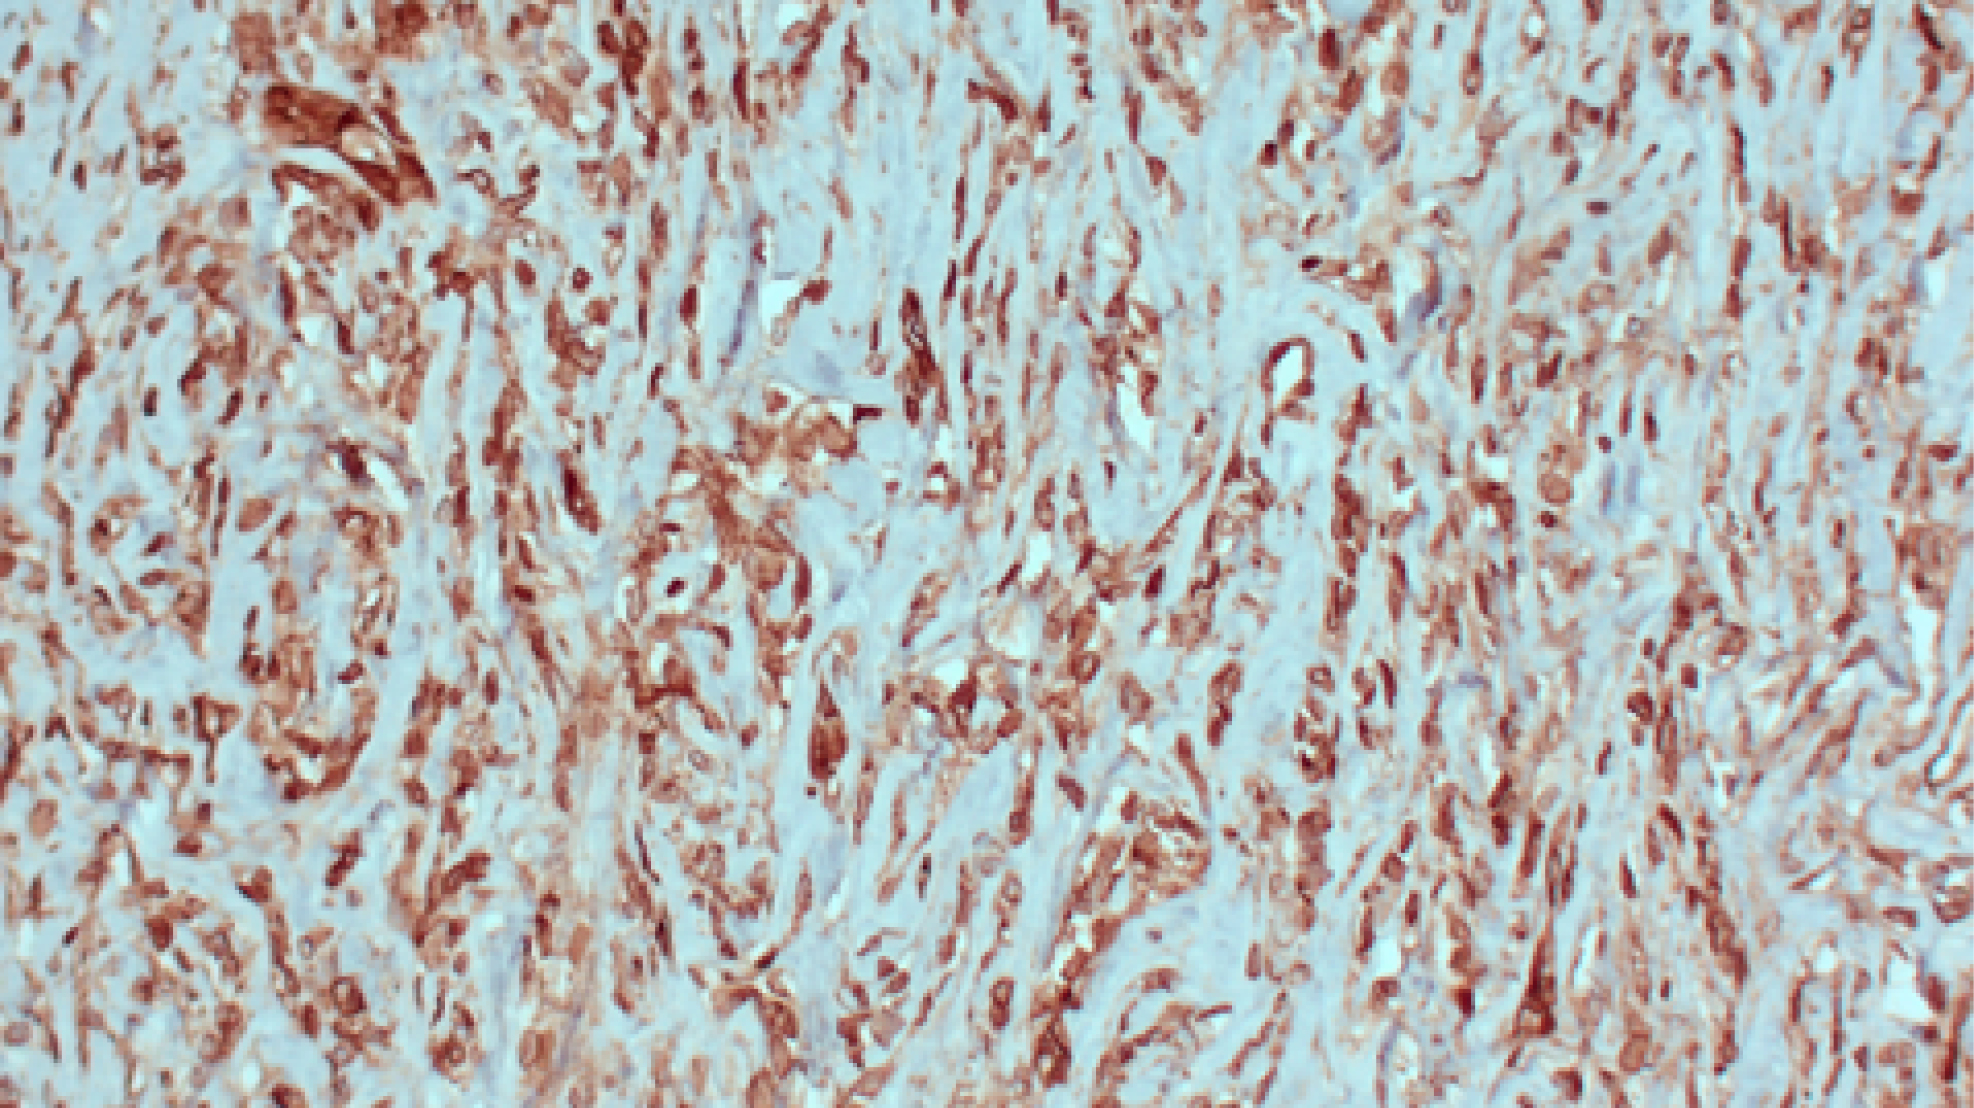

Иммуногистохимическое исследование. Диффузная цитоплазматическая экспрессия CD34, цитоплазматическая экспрессия aSMA в единичных клетках. Клетки опухоли негативны к Beta-Catenin, HMB-45, CD31, DOG1, EMA, S100 (рис. 6).

Рис. 6. Микропрепарат: диффузная цитоплазматическая экспрессия CD34, цитоплазматическая экспрессия aSMA в единичных клетках.

Fig. 6. Microscopy: diffuse cytoplasmic expression of CD34, cytoplasmic expression of aSMA in single cells.

Заключение: иммуногистохимическая картина наиболее соответствует солитарной фиброзной опухоли печени.